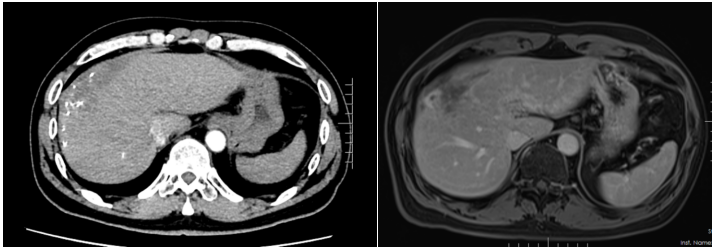

患者入院时诉说了自己与晚期肝癌对抗的痛苦与不易,同时也表明了与病魔抗争到底的决心。入院后,龙奎副主任医师立即为患者完善了CT、MRI+MRCP,ICG等检查,经过术前多学科MDT讨论后,认为患者肝癌转化效果满意,可以手术治疗。

由于患者肝癌位置特殊,肿瘤占据肝脏多个亚段,并且门静脉伴有海绵样变,手术中出血风险较大。另外,如大范围切肝,残余健全肝脏较少,术后有肝功能衰竭风险。为了保证患者手术质量安全,肝胆胰外科三病区高度重视,龙奎副主任医师组织科室详尽讨论了患者手术方案,在老专家孙敏教授、滕毅山教授、莫小华教授的鼎力支持下,最终决定采用腹腔镜微创手术方式完成手术,以最小的创伤让患者获得最大的收益。

手术中,由于患者有门静脉海绵样变特别容易出血,转化治疗后肝内管道走行变异,手术过程尤其艰难。龙奎副主任医师、董文志副主任医师、孙翊程医师与昆医大附二院优秀的麻醉团队、手术室护士团队通力合作,利用医院先进的荧光腹腔镜导航辅助,精准地完成了腹腔镜下肝IVb段+V段+胆囊切除术,历时5个小时,出血量200ml。